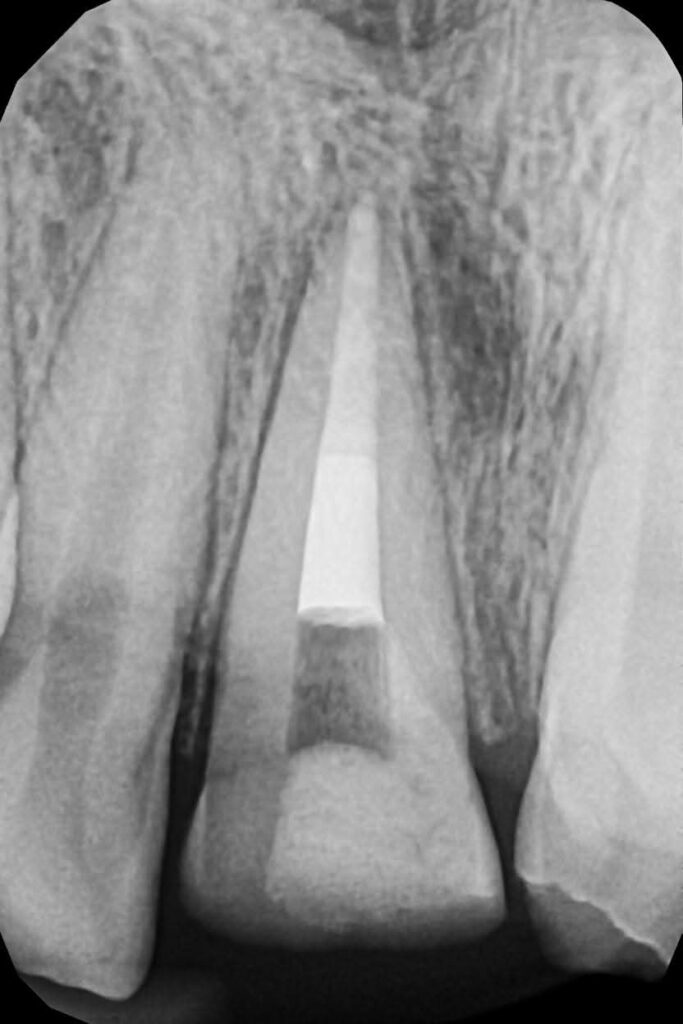

Proportionality relates to the width-to-length ratio and the relationship between anterior teeth. The ideal width/length ratio for central incisors is approximately 75–80%, and the apparent width proportion between anterior teeth often follows the golden proportion (~62%), although modern aesthetic dentistry prefers the concept of Recurring Esthetic Dental (RED) proportion for more natural results.

1. Tooth dominance (central incisors dominant)

2. Line angle positioning to control perceived tooth width